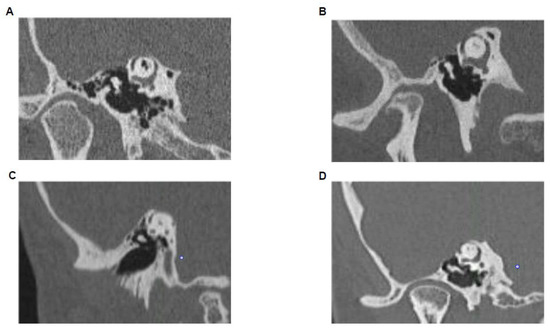

2.4. High-Resolution CT-Scan